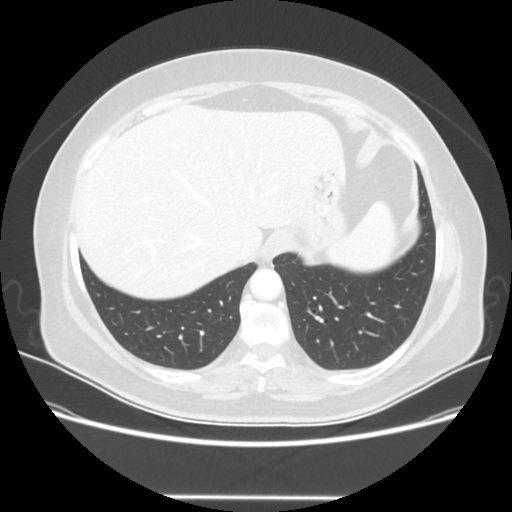

Original VENOUS CT scan

Full window (WL 1023.5, WW 4095 β†’ Low βˆ’1024, High +3071)

Lung window (WL -600, WW 1500 β†’ Low βˆ’1350, High +150)

Mediastinum window (WL 40, WW 400 β†’ Low βˆ’160, High +240)